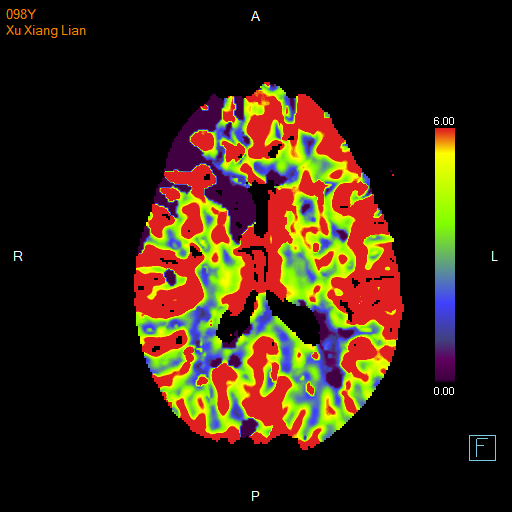

进一步的血管检查(CTA+CTP)发现了更严重的问题:王奶奶的左侧颈内动脉完全闭塞——这是脑梗中最凶险的类型之一,意味着大脑主要供血通道被切断,随时可能危及生命

颅脑 CTP